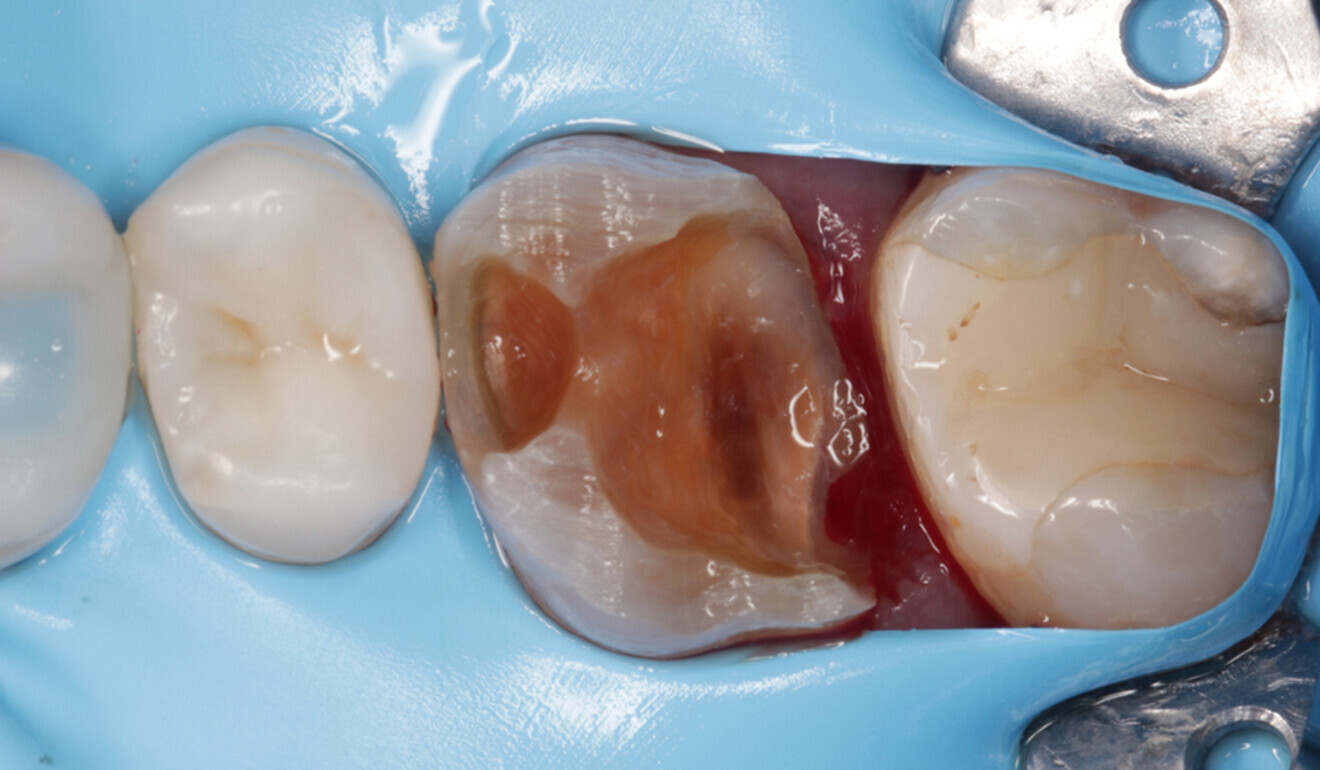

In accordance with the European Society of Endodontology’s guidelines on the management of deep caries,10 the deepest part of the cavity was cleaned under full dental dam isolation (Nic Tone, MDC Dental; Fig. 6). Carious tissue excavation was carried out using round burs and then the enamel and dentine were air abraded with 50 μm aluminium oxide (MicroEtcher IIA, Danville Materials). Multiple cracks, penetrating through the enamel and partially the dentine, had occurred within the mesial and palatal walls. The presence of cracks crossing the amelodentinal junction is an absolute indication for cuspal coverage.8, 11

Fig. 6: Dental dam newly placed in the interproximal area. Full isolation is essential for the excavation of the infected dentine in the deepest part of the cavity. (Image: Kuraray Noritake Dental)